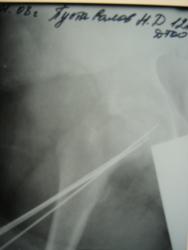

Теперь понятно, все таки основной признак - расширение зоны роста, а как вторая сторона, она попала в зону интереса или работали на МРТ только с одной конечностью?

Другая конечность не поражена, МРТ делали таза и тазобедренных суставов

img_1993.jpg